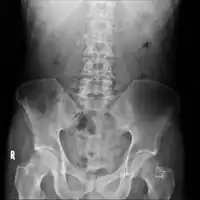

On CT scan, pancreatic and bile duct dilatation, atropy of pancreas, multiple calcifications of the pancreas, and enlargement of pancreatic glands can be found.[12]

Chronic calcific pancreatitis

Acute on chronic pancreatitis